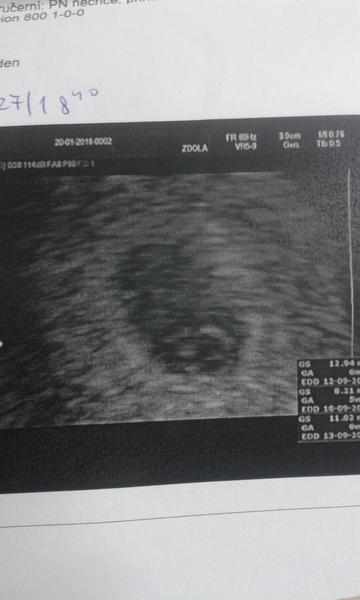

Dobre dopoledne tehulky, tak mi mame po ko. Je videt plodovy obal a cosi se tam uz rysuje. Michaela 110 jsme uplne ve stejnem dni 6+1 😉 chodim, co tyden na ko, doktor mi chce delat radost a uklidnovat me, kdyz jsme se tak dlouho snazili, za tyden uz by melo jit videt embryo. Jinak holky, cvicit chodim, mam posledni lekci s trenerem a pak uz sama, ale spis je to takove protahovani a lehle posilovani, plus light kardio. Dokud to pujde, tak budu chodit. Rada se pridam do soukrome skupiny, ale pouze ma MK. Facebook jsem smazala. Zaspamuju vam tu fotku jestli nevadi 😉